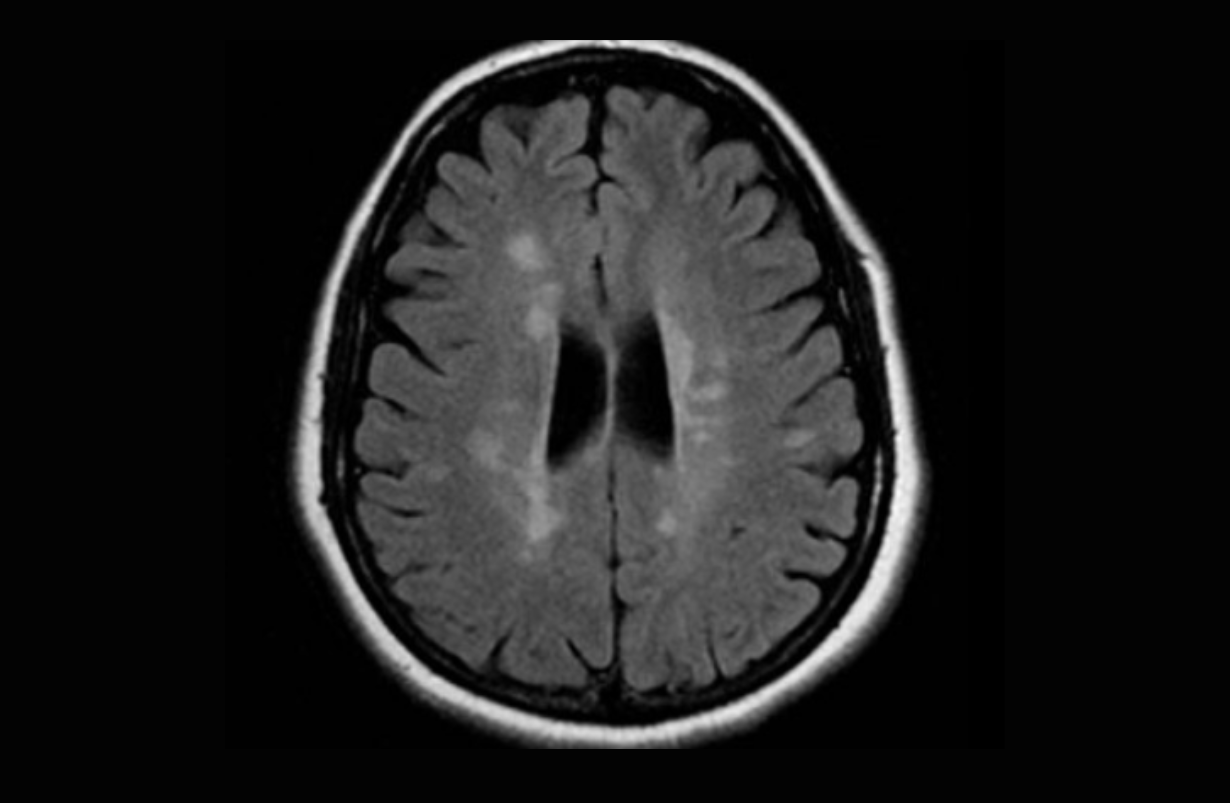

Alzheimers disease

Alzheimers disease, or pre-senile dementia is characterized by changes in thinking, behavior, and feeling. Neurophysiologically, Beta amyloid plaques develop in the central nervous system, and Tau proteins become disrupted, eventually causing cell death. One positive study involves Kriya yoga, with chanting, hand movements and devotional activities were as effective in restoring default mode networks as the most effective memory enhancement programs. References: McCaffrey R, Park J, Newman D, Hagen D. The effect of chair yoga in older adults with moderate and severe Alzheimer's disease. Res Gerontol Nurs. 2014 Jul-Aug;7(4):171-7. Lavretsky H Complementary and alternative medicine use for treatment and prevention of late-life mood and cognitive disorders. Aging Health 2009;5, 61–78. Gothe NP , Kramer AF , McAuley E The effects of an 8-week Hatha yoga intervention on executive function in older adults. J Gerontol A Biol Sci Med Sc 2014; 69, 1109–1116. Hariprasad VR , Koparde V , Sivakumar PT , Varambally S , Thirthalli J , Varghese M , Basavaraddi IV , Gangadhar BN Randomized clinical trial of yoga-based intervention in residents from elderly homes: Effects on cognitive function. Indian J Psychiatry 2013; 55, S357–S363. • Eyre HA, Acevedo B, Yang H, et al. Changes in Neural Connectivity and Memory Following a Yoga Intervention for Older Adults: A Pilot Study. J Alzheimers Dis. 2016;52(2):673-84. doi: 10.3233/

Epilepsy

Epilepsy is a brain disorder characterized by abnormal and excessive brain activity producing non-volitional behavior which may be gross uncoordinated flexion and extension of different groups of muscles (tonic-clonic), or total stillness (absence). Yoga, especially meditation has been found helpful in reducing the incidence as much as 62%. One successful form is Sahaja yoga in which the meditator first becomes calm and attentive to the chakras, then entertains gratitude and forgiveness to all beings including onesself, and then feels various parts of his or her body

Multiple Sclerosis

A central nervous system condition in which small plaques appear in the white matter (conducting parts) of the brain and spinal cord, interfering with nerve conduction. Resultant effects may be motor, sensory and/or cognitive/emotional. BENEFICIAL POSES: Restorative yoga. EXPLANATION: There are basically two types of MS: 1. Relapsing and Remitting, in which there are intermittently greater periods of symptoms and signs, followed by periods of relatively less involvement. The remitting phase may leave people more disabled than they need to be, as an advancing army leaves famine in its wake. Yoga can remediate that disability quite well. 2. Progressive, in which there is an irregular but consistent worsening of symptoms and signs. Yoga is shown to be of value in fighting the fatigue that is quite disabling in this form of MS. REFERENCE: "Randomized controlled trial of yoga and exercise in multiple sclerosis. Oken BS, Kishiyama S, Zajdel D, Bourdette D, Carlsen J, Haas M, Hugos C, Kraemer DF, Lawrence J, Mass M. Neurology. 2004 Jun 8;62(11):2058-64. Fishman, L and Small, E. Yoga for Multiple Sclerosis. Demos Medical Publishing, New York 2007.